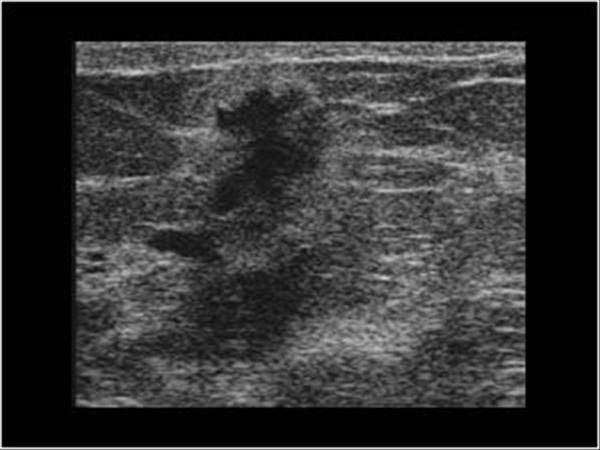

Ung thư vú

Ung thư vú - Ảnh 3

» Thông tin: Nữ giới – 59 tuổi.

» Lâm sàng: Khối tuyến vú.